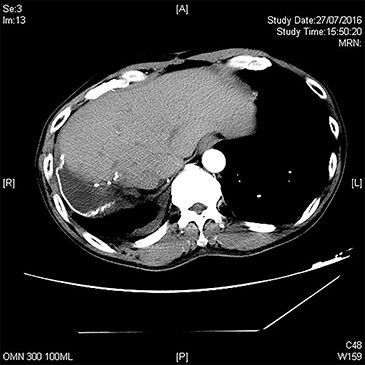

A repeat CT after TACE and PVE though showed sufficient hypertrophy of left liver, it also revealed significant growth of tumor with invasion to right lower lobe of lung through diaphragm (Fig. 1). Operation proceeded with a Mercedes-Benz incision with patient placed in supine position. Tumor was found to invade through medial part of diaphragm to right lower lobe of lung for 3 cm depth. Anterior approach right hepatectomy was performed [4]. Diaphragm was divided surrounding the tumor invasion site. En bloc wedge resection of the involved right lower lobe of lung was performed with endovascular staplers via the diaphragmatic opening. The diaphragmatic defect was closed with Goretex mesh (Fig. 2). Patient made an uneventful recovery and went home on Day 8 after surgery. Pathology confirmed a 12.5 cm poorly differentiated HCC invading through diaphragm to lung (Figs 3 and 4). Both resection margins at liver and lung were >1 cm. AFP decreased to 3 μg/l after operation.

CT showing a large hepatocellular carcinoma invading through diaphragm into lung base. (A) axial view, (B) coronal view and (C) sagittal view. Hyperdense material within liver is lipiodol deposits after previous TACE.